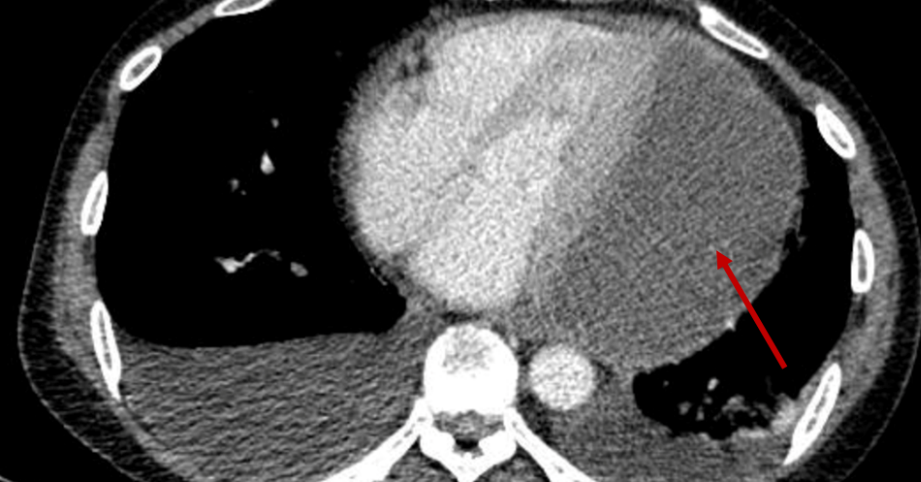

Mới đây, một bé trai 13 tuổi tại TP.HCM, vốn khỏe mạnh, đã rơi vào trạng thái hôn mê sâu, suy hô hấp và trụy tim mạch sau khi ngồi hơn một giờ trong ô tô đóng kín, dù có bật điều hòa. Bé được cấp cứu tích cực, đặt nội khí quản, thở máy, điều trị chống phù não và vận mạch. Sau 5 ngày, bệnh nhi hồi phục dần và dự kiến xuất viện nếu không có biến chứng thần kinh lâu dài.

Nguyên nhân được xác định là ngộ độc styrene, do bên trong xe có một chai hóa chất hàn nhựa chứa styrene.